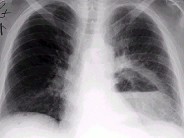

- 单项选择题男,36岁, 胸痛半月伴发高热,胸片发现占位性病变, CT检查如图,最可能的诊断为 ( )

A、左下肺肺脓肿

B、左下肺癌并空洞形成

C、左侧胸腔积脓

D、左下肺囊肿

E、左下肺肺炎